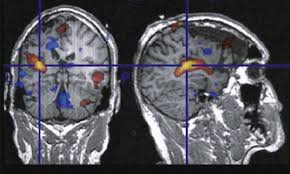

Ein Aneurysma vor allem im Gehirn kann angeboren sein. Da das Schiff beginnt sich aufzublähen wird es wahrscheinlicher zu platzen. Niemand kann vorhersagen wann ein Aneurysma platzt und Leck Blut in die umliegenden Gebiete. Solange ein Aneurysma noch klein und intakt ist das Gefäß also keine Risse hat verursacht es häufig keinerlei oder nur unspezifische Beschwerden wie Kopfschmerzen oder Übelkeit. Wenn ein Blutgefäß erweitert oder Ballons durch Schwächung Wände heißt es ein Aneurysma. Je nach Größe und Lage des Aneurysmas im Gehirn können jedoch auch Beschwerden auftreten. Ein Aneurysma ist eine krankhafte Aussackung einer Schlagader. Fachleute gehen aber davon aus dass Aneurysmen mit einem Durchmesser unter sieben Millimetern nicht sofort behandelt werden müssen sondern beobachtet werden können. Je nach Größe und Ort sind weitere Symptome möglich.

Nicht rupturierte intrakranielle Aneurysmen finden sich bei etwa drei Prozent der Erwachsenen. Ein Aneurysma ist eine krankhafte Gefäßausstülpung also eine örtlich begrenzte Erweiterung einer Arterie. Ein Aneurysma ist eine krankhafte Gefäßausstülpung die sich an den hirnversorgenden Gefäßen zumeist an Gefäßaufzweigungen befindet. Die meisten Gefäßaussackungen im Kopf entdecken Ärzte durch Zufall oder weil sie Symptome wie beispielsweise Doppeltsehen verursachen. Täglich im Kühlschrank aufbewahren. Aber es lässt sich nicht ganz ausschließen dass auch solche kleinen Aneurysmen reißen. Niemand kann vorhersagen wann ein Aneurysma platzt und Leck Blut in die umliegenden Gebiete.